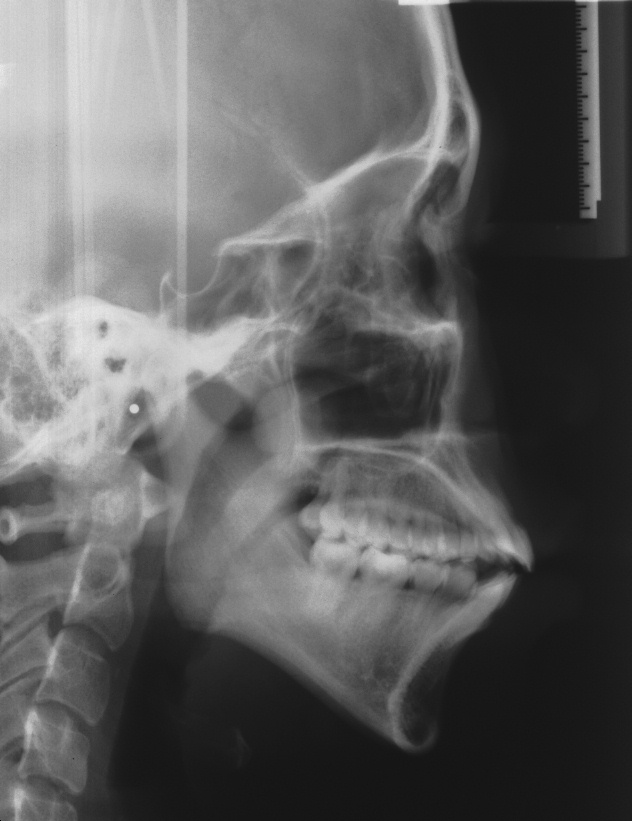

치료 전 사진입니다.